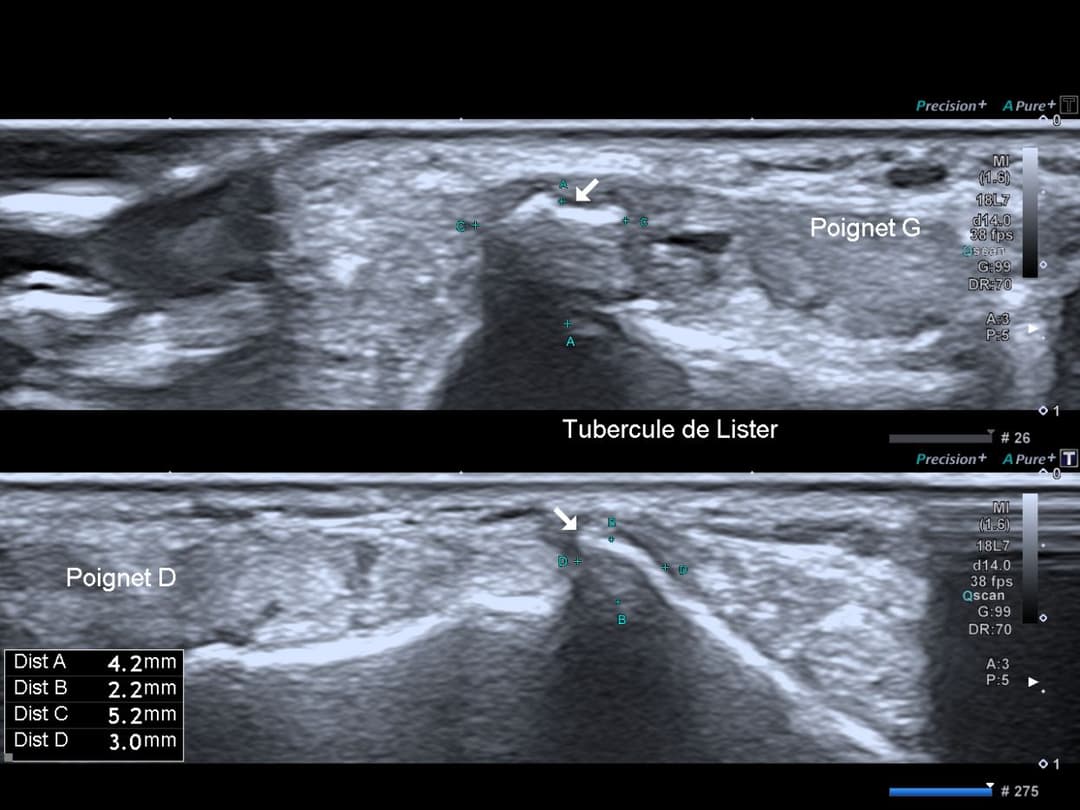

Légère hypertrophie et remaniement du tubercule de Lister.

Aspect remanié et hypertrophie du tubercule de Lister du côté pathologique pouvant favoriser le conflit tendineux